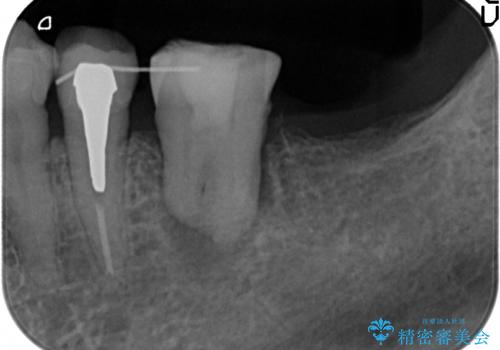

親知らずの移植 4年半経過症例 70代女性

- 親知らずの移植治療から4年半経過した患者様です。

他の歯の治療をご希望され、数年ぶりに来院して下さいました。

移植した親知らずは全く問題ないそうで、「まるで自分の歯のようです。本当にすごい技術ですね。」とおっしゃって下さいました。

歯肉の腫脹や退縮、動揺も認められませんでした。

4年半前に行った自家歯牙移植に大変ご満足頂き、ご家族も紹介して下さいました。

自家歯牙移植は40歳以上の場合、若年者に比べ成功率が低くなるとの報告もありますが、状態によっては移植が可能な場合もあります。